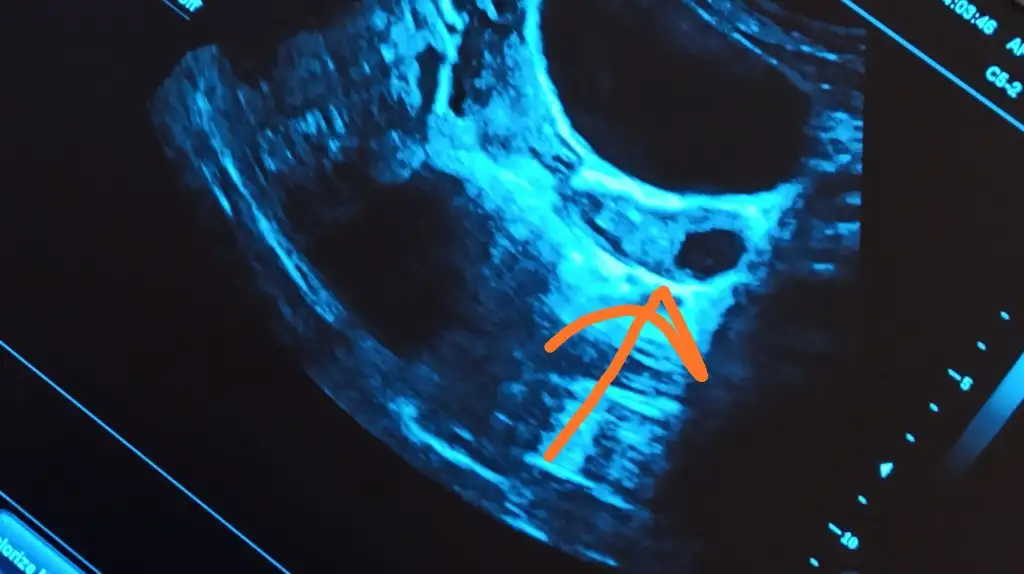

Kasigim dun kotuydu bugun biseyim yok lekelenmede yok ama usgde gordum bariz belliydi bak cektim fotosunu ataym

Eklentiler

• IMG_20200902_171100.webp